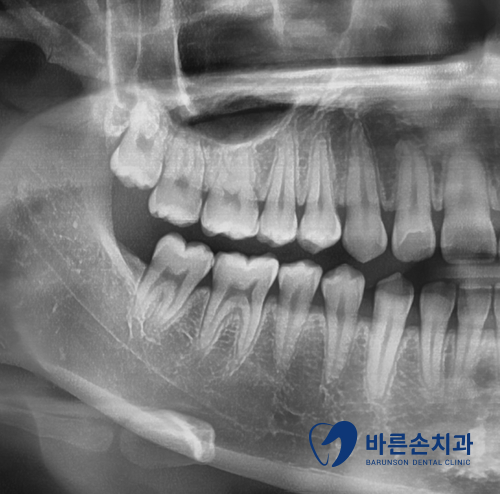

그럼 엑스레이로 상태를 확인해 볼까요?!

1)정상잇몸 사진은 치석이 보이지 않고 치조골(잇몸뼈)이 수평으로 일정하게 이어진 것을 볼 수 있습니다.

2)치주질환 잇몸 사진은 치석이 보이고 치조골 높이가 낮아지면서 잇몸뼈가 수직으로 흡수된 것이 보입니다.

잇몸뼈가 많이 녹을 수록 치아가 많이 흔들리게 되고 이런걸 바로 ‘풍치’ 라고 합니다.

치아가 충치도 없고 건강해도 치아를 잡아주는 잇몸뼈가 약해지면 치아를 뺄 수 밖에 없어집니다.

사진 속 환자분도 결국 발치를 했답니다…너무 안타깝죠ㅠㅠ

치주질환 엑스레이